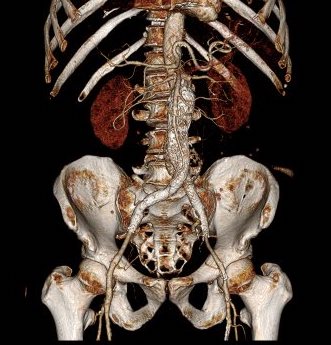

Looking back at his records, for three years he had multiple CT scans for abdominal pain showing the AAA and a well documented record of growth of about 2-3mm annually -the normal growth rate. He asked me to prognosticate and so I relayed that 4.7cm in 2017 with a 3mm growth rate, we would be operating in 2020. The anatomy was favorable with a long infrarenal neck and good iliac arteries for distal seal and access. He was quite anxious as whenever he had abdominal pain, his local doctors would discuss the AAA and its risks or order a CT. After a long discussion and considerable lobbying by the patient and family, I agreed to repair his 4.7cm AAA.

The EVAR was performed percutaneously. No endoleak was detected by completion arteriography (figure). He was soon discharged and was grateful. In followup, CT scan showed excellent coverage of the proximal and distal zones and absence of type III endoleaks. There was increased density to suggest a type II leak, but his inferior mesenteric artery was not the source of it. over a three year period, his aneurysm sac continued its 2-3mm of annual growth despite the presence of the the stent graft.